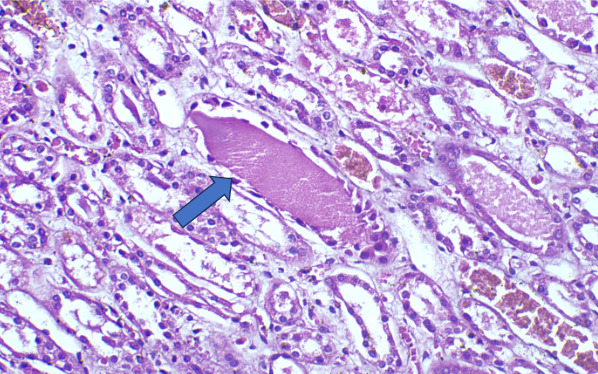

On Light microscopy, The H &E-stained sections of renal biopsy showed features of acute tubular epithelial cell injury with swollen, attenuated lining epithelium. Numerous tubules showed pink to red brown casts in the lumen which were grainy to globular and ropy at places. (Figure 1). The casts appeared weakly PAS positive (Figure 2) and fuchsinophilic on MT stain (Figure 3). On IHC, these casts gave positive staining for myoglobin (Figure 4).

On Light microscopy, Renal biopsy shows features of acute tubular injury (ATI) with attenuation of tubular epithelial cells, cytoplasmic vacuoles, brush border loss and sloughed out intratubular epithelial cells.3,4,13

According to one study, other associated finding may be of arterial sclerosis and deposition of calcium oxalate.3 Myoglobin casts are usually appeared eosinophilic to brown granular in H&E stain, are weakly PAS positive and fuchsinophilic in MT stain. Differential diagnosis of Myoglobin casts includes other pigment casts like haemoglobin casts and bile casts.5,11–13